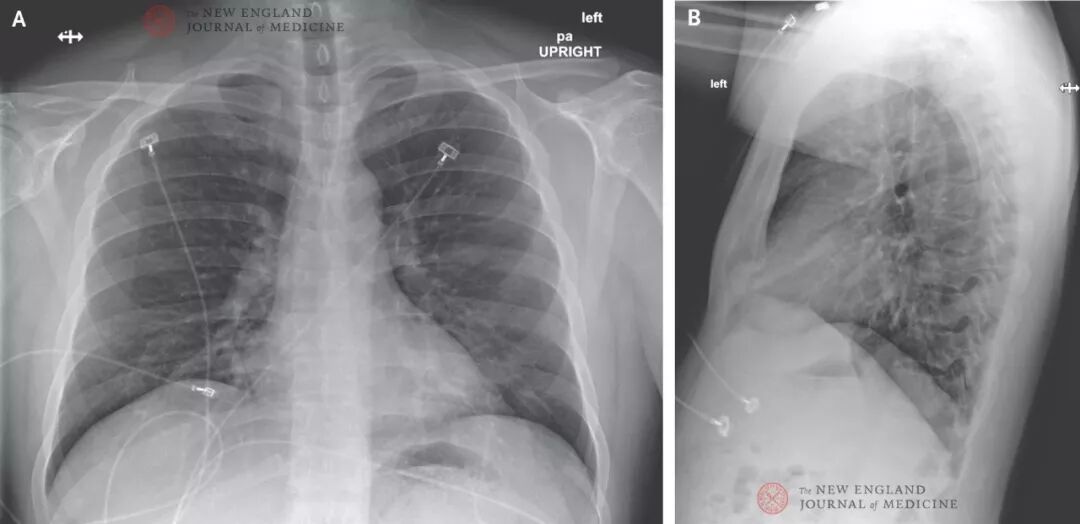

在患者住院第6日(发病第10日),第4次胸片检查显示双下肺条索状阴影。胸片结果与不典型肺炎诊断吻合(图5),双肺听诊提示有水泡音。根据患者的影像学检查结果,开始吸氧的治疗决策,患者的持续发热,多个样本的2019-nCoV RNA持续阳性结果,以及有报道指出其他患者在与该患者的影像学肺炎一致的时间段发生重度肺炎[3,4],因此临床医师将一种试验性抗病毒药进行了特许用药。住院第7日晚上,这名患者接受了remdesivir(一种处于研发阶段的核苷酸类似物[10,11])静脉输注,无明显副作用。第7日晚上,得到连续阴性的降钙素原水平和耐甲氧西林金黄色葡萄球菌PCR阴性结果后,停用万古霉素,第8日停用头孢吡肟。图4. 2020年1月24日后前位胸片(发病第9日,住院第5日)。左肺下叶毛玻璃样改变加重,提示肺炎可能。

图5. 正位胸片和侧位胸片,2020年1月26日(发病第10日,住院第6日)。肺叶底部呈持续毛玻璃样斑点,提示可能为非典型肺炎;毛玻璃样改变随时间推移不断增强。